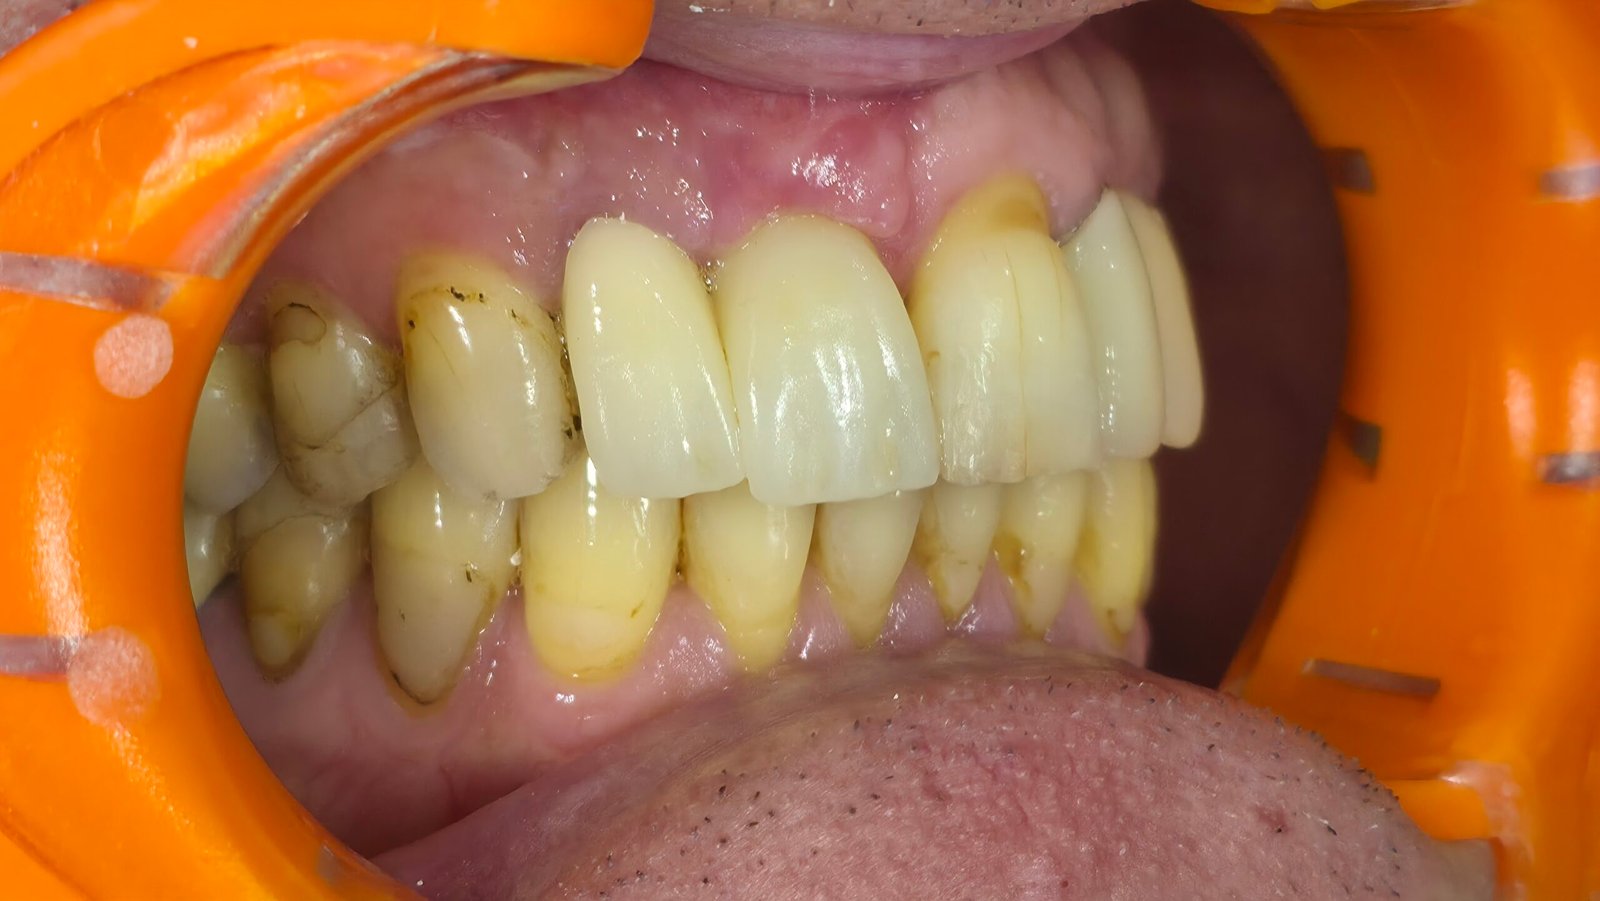

Réhabilitation esthétique après orthodontie : full-zircone & disilicate de lithium

Une jeune patiente arrive en fin de traitement orthodontique pour un déficit esthétique.

La difficulté réside dans la réalisation de prothèses différentes dans le même secteur : jongler avec la full-zircone et le disilicate de lithium.

Ce challenge fut le sujet de mon mémoire du DU d’esthétique de Strasbourg en 2008.

L’expérience et l’investissement dans le digital depuis 2017 rendent le résultat plus prévisible.